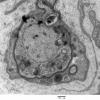

PERIPHERAL NEUROPATHY

18 HEREDITARY DISORDERS

Charcot-Marie-Tooth 1 (CMT-1) (8)